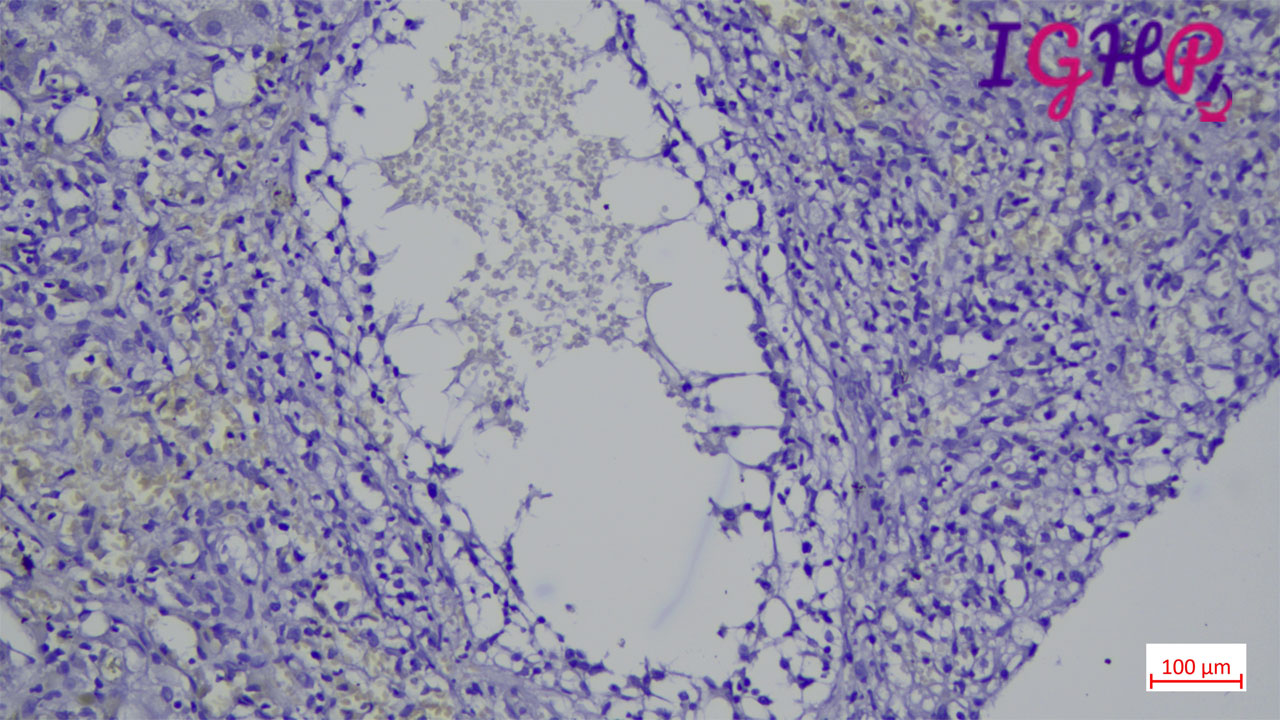

Microscopic Images-

Microscopic examination showed an areas of perivenular hepatocyte loss with prominent central perivenulitis.